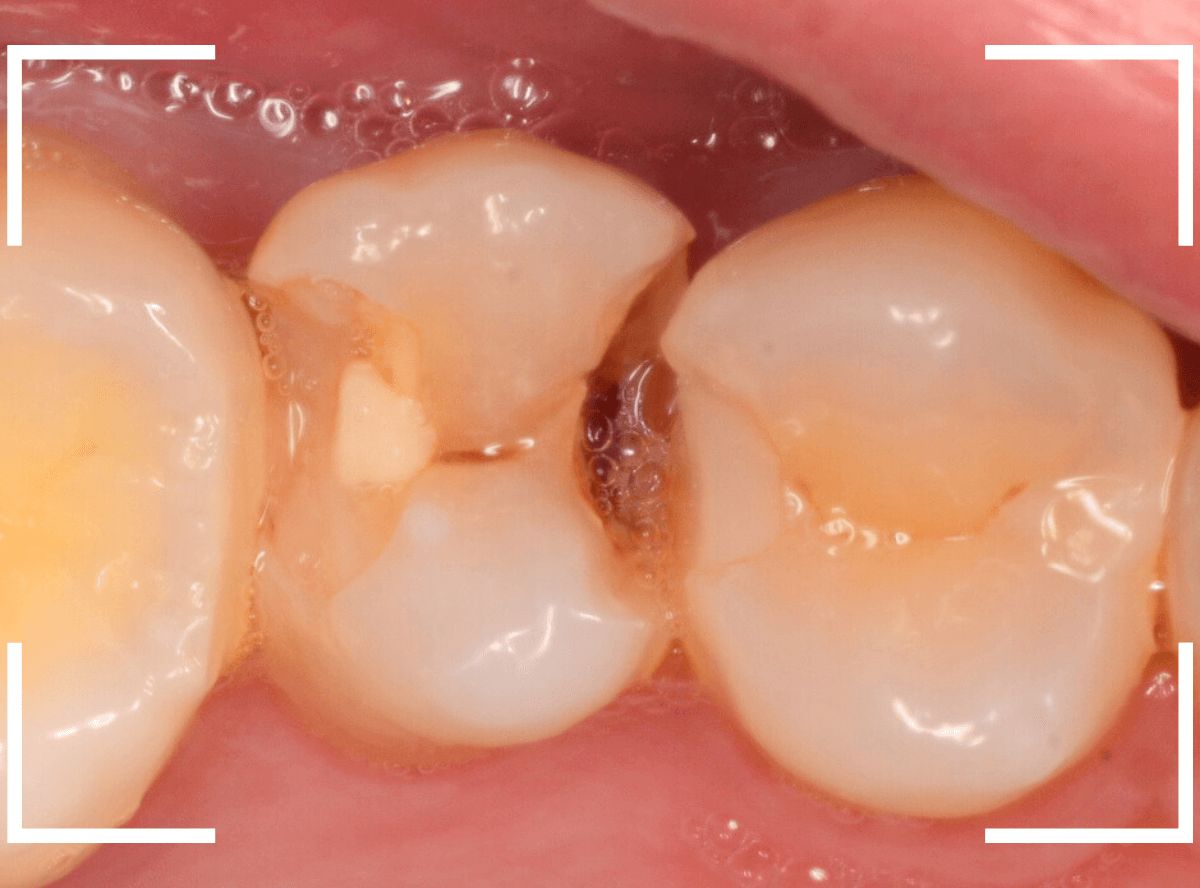

Case.4 2年間メンテナンスを中断している間に、深く虫歯が進行!

定期メンテナンスを2年間中断後に、来院された患者さんです。

見た目は手前の歯との間の小さな虫歯に見えますが、

「普段は痛くない」

「食事の時に物がつまる」

「物がつまった時に噛むと痛い」

・・・と、自覚症状は乏しいが、実際は大きな虫歯の場合の症状あるあるの訴えでした。

レントゲン写真で虫歯の状況を確認します。

赤い線が虫歯の部分、青い線が歯の神経の部分です。

思った通り、入り口の小さなすき間の中は、神経まで達してしまいそうな大きな虫歯になっていました。

歯を削り始めると、すぐに大きな穴が出てきました。

ある程度虫歯を除去したところで、う蝕検知液で染め出してチェックします。

まだまだ虫歯が残っていますね。

取り残しがないように、しっかり除去する必要があります。

虫歯を全て除去したところです。

神経が少し見えるところまで虫歯が進行していました。

神経を保護するお薬をつめた後、蓋をしてしばらく痛みが出ないか、経過観察します。

痛みが出て止まらないようでしたら、神経を除去する治療が必要になります。

定期メンテナンスを中断しなければ、このような状況にはならなかった事が本当に悔やまれます。